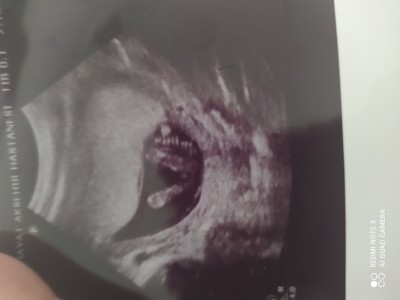

Cinsiyet sizce nedir ? (RESİMLİ)

kizlar 15 haftalık gebeyim sizce cinsiyet nedir ?

Hem kese şekli hemde çıkıntısı erkek diye bağırıyor. Bende erkek bekliyorum.